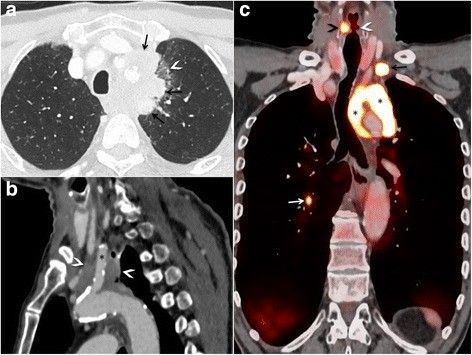

Мужчина жаловался на прогрессирующую дисфагию, острую дисфонию и снижение массы тела на 3 кг, при медосмотре у него была обнаружена опухоль в верхней доле левого легкого с инфильтрацией средостения — 7-миллиметровый гиперметаболический узелок в контрлатеральной нижней доле, лимфоаденопатия средостения и левой надключичной области. При дообследовании (ФБС) и проведении биопсии диагностирован плоскоклеточный рак легкого T4N3M1 (рис. 1).

Рисунок 1 [1].